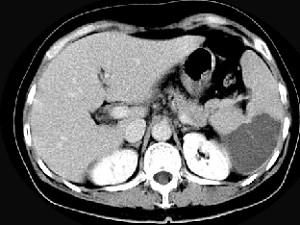

女、54岁,左上腹痛,CT检查如图,最可能的诊断是 ( )A、脾血管瘤B、脾转移瘤C、脾脓肿D、脾梗死E、脾淋巴瘤

问题 女、54岁,左上腹痛,CT检查如图,最可能的诊断是 ( )

选项 A、脾血管瘤 B、脾转移瘤 C、脾脓肿 D、脾梗死 E、脾淋巴瘤

答案 D